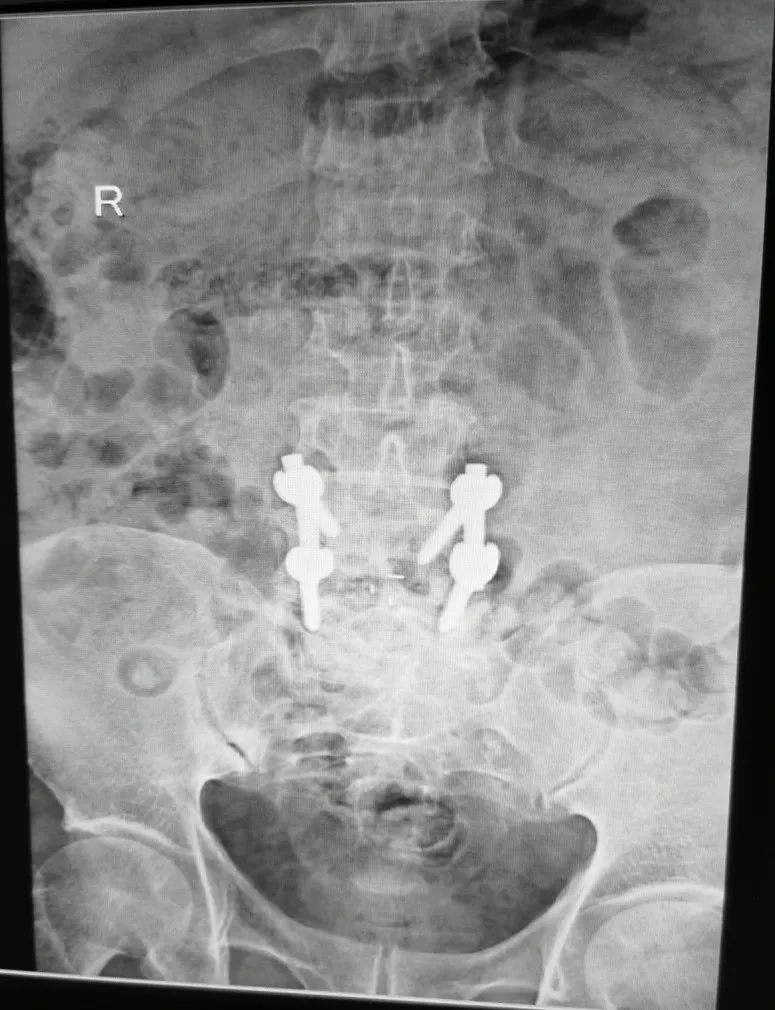

腰椎内固定术后影像:CT可见椎体多个低密度灶。

▲X光片